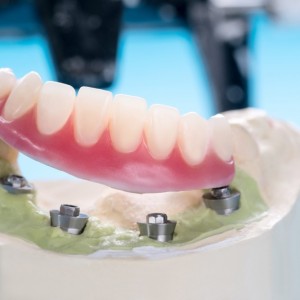

All treatments’ goals were achieved in very short time and with maximum aesthetics during the treatment with his clear aligners providing him perfect cleaning access with predictable and accurate technology. Patient received fixed retain- ers for anterior teeth and re- movable clear aligners for night wear (figs. 17, 18).